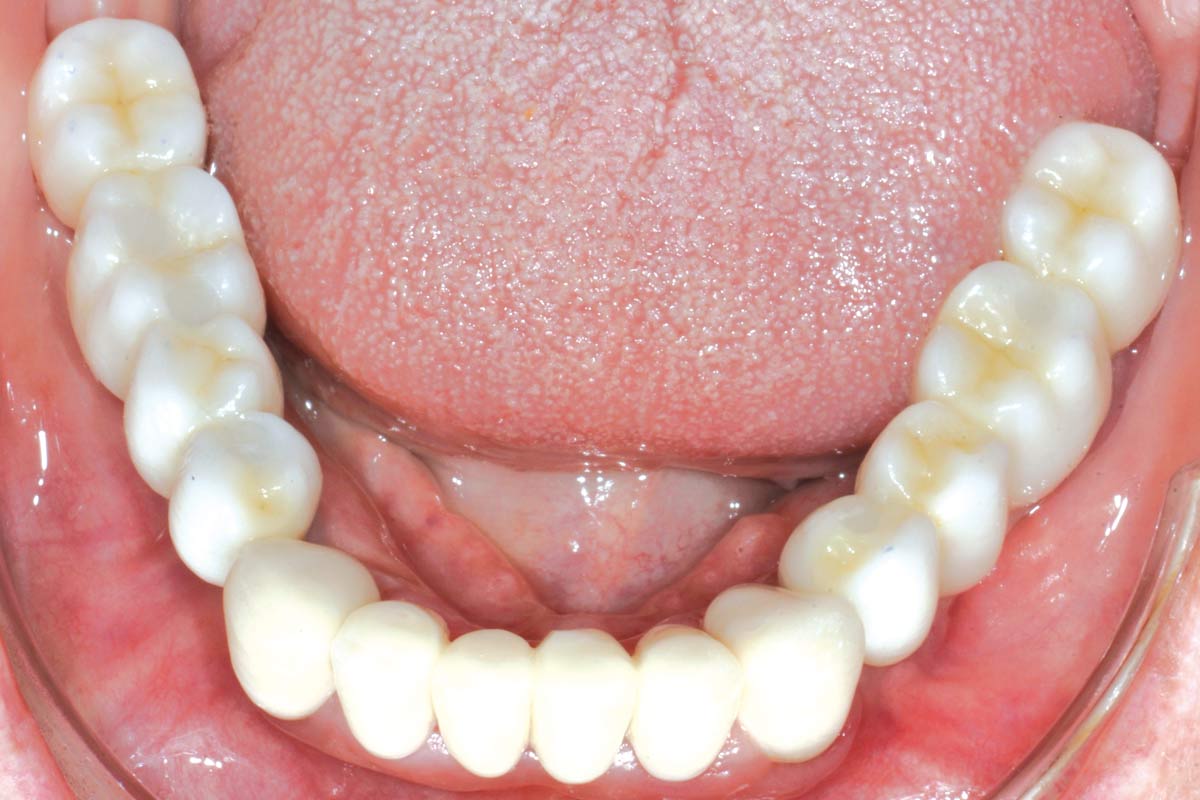

16/16 - Placement of definitive crownsPeri-implant soft tissue thickening with mucoderm® - Dr. F. Rojas-Vizcaya